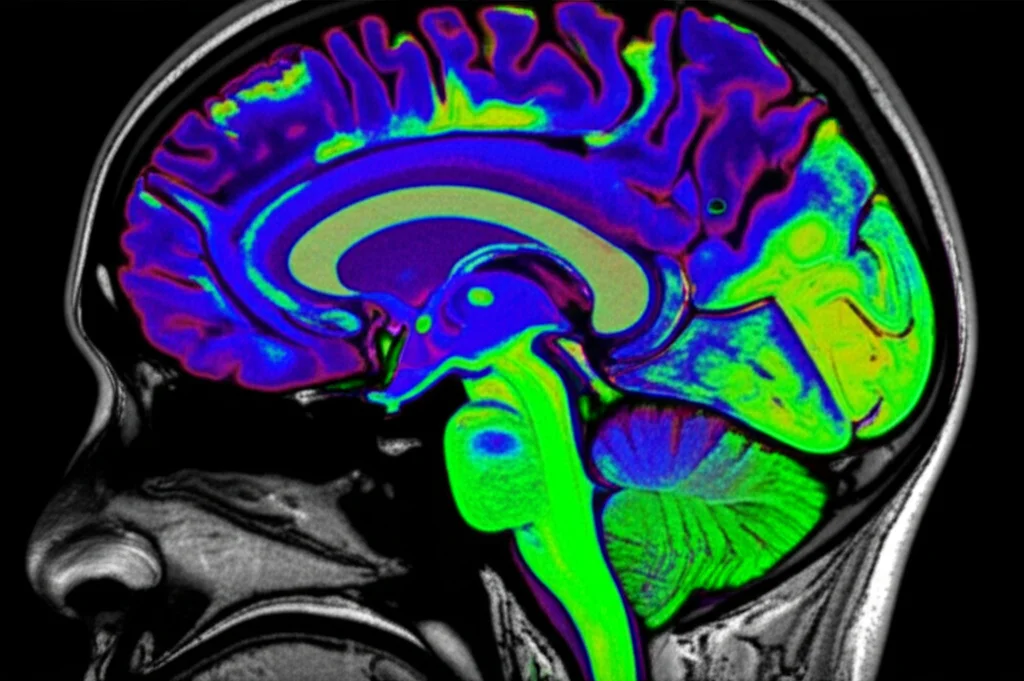

Sapete, il cuore del problema nel Parkinson è la perdita di quei neuroni nella substantia nigra che producono dopamina, un neurotrasmettitore fondamentale per il controllo del movimento. Le terapie farmacologiche, come la levodopa, funzionano bene all’inizio, mimando l’azione della dopamina, ma col tempo perdono efficacia e possono causare effetti collaterali pesanti, come le discinesie (movimenti involontari). Da qui nasce l’idea: perché non provare a sostituire direttamente le cellule mancanti?

- Possiamo ripristinare in modo consistente i livelli di dopamina nel putamen (un’area chiave del cervello colpita dal Parkinson) a livelli quasi normali?